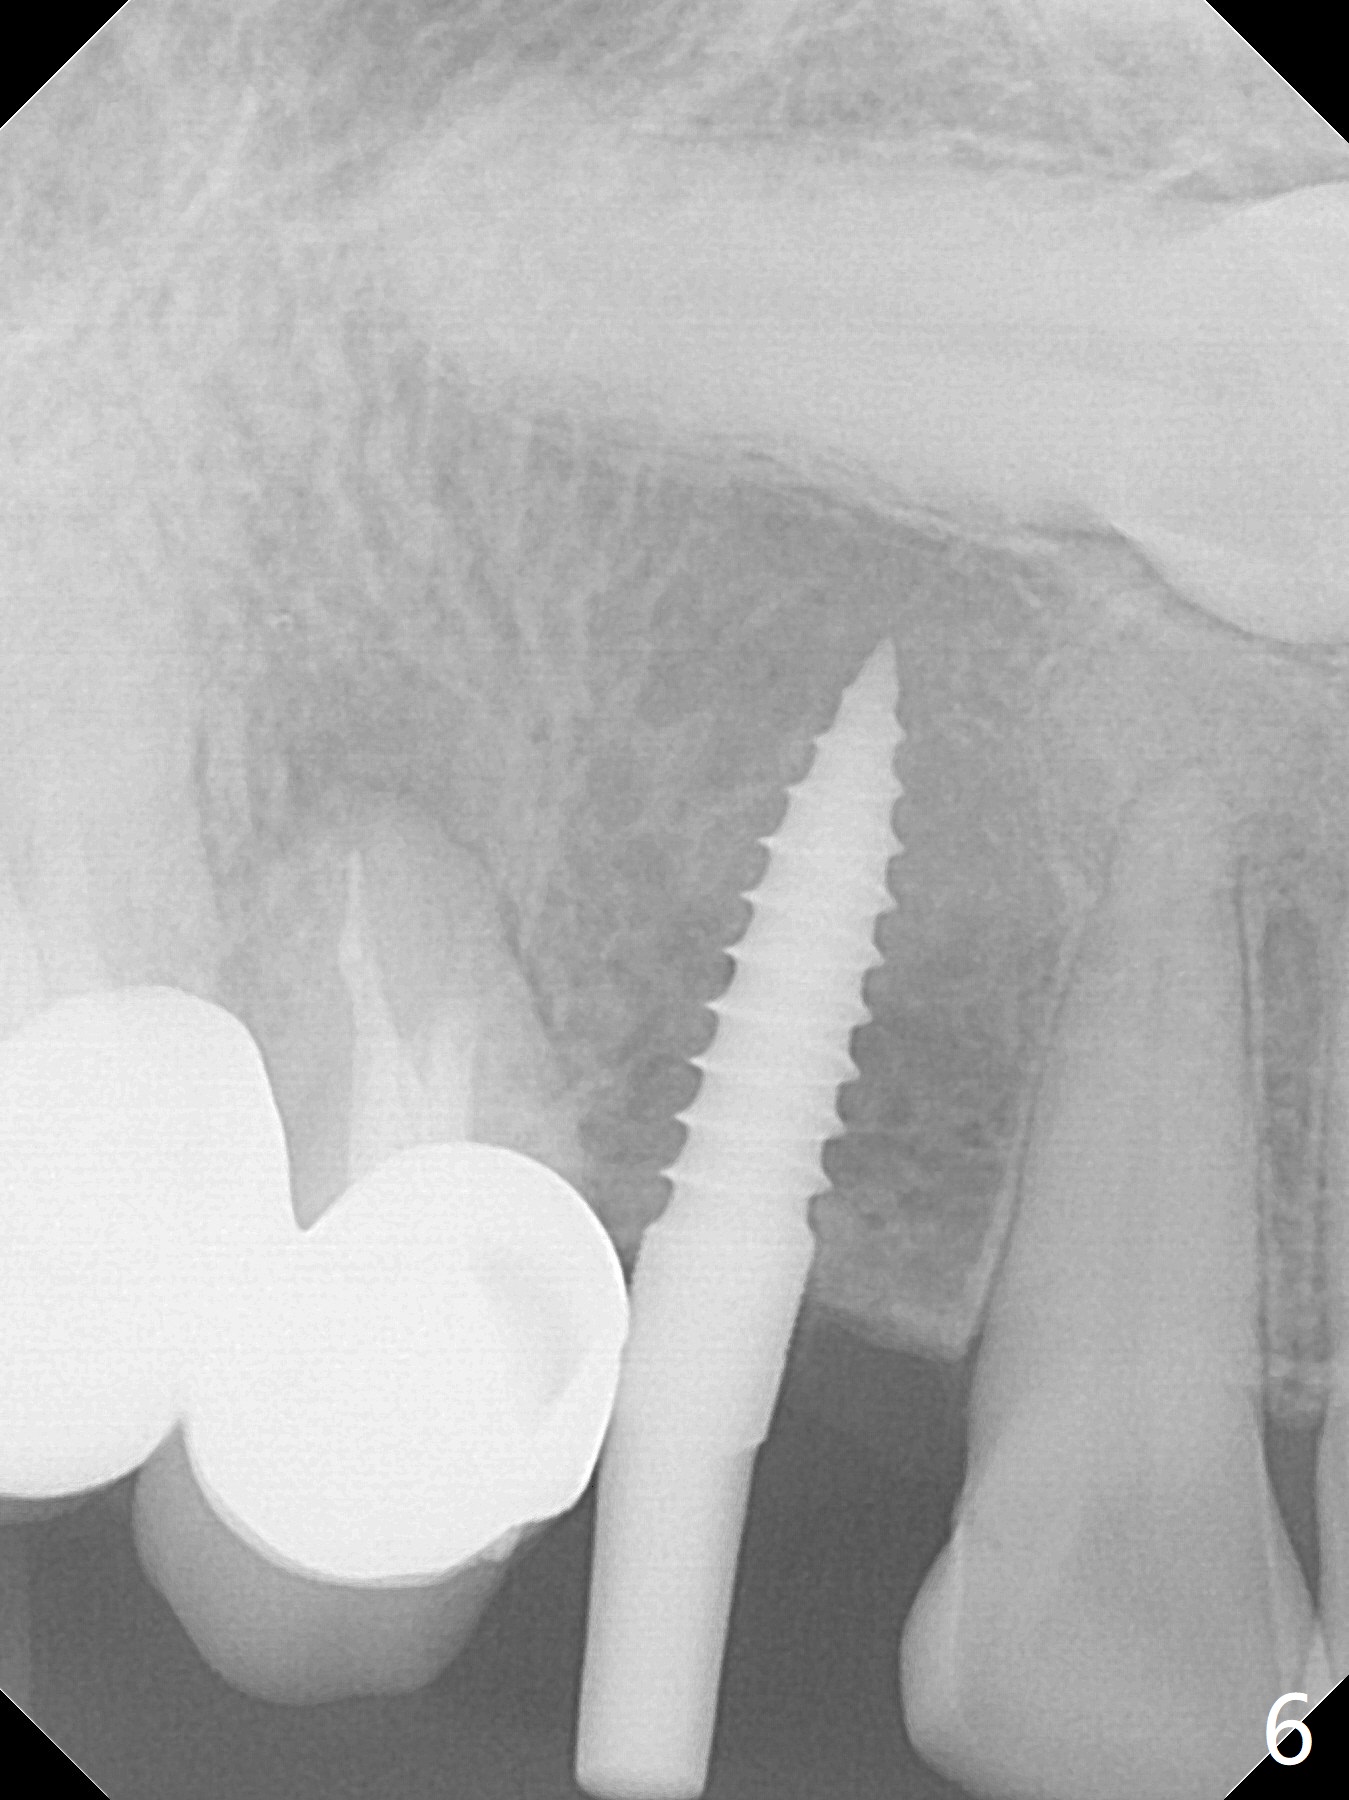

After removal the pontic of a cantilever FPD (Fig.1), a residual root is found at #6 with the buccal concavity (Fig.2 *). The ridge is narrow with flap elevation (Fig.3). PA taken with a 1.2 mm drill for 14 mm shows a horizontally impacted canine (Fig.4: #6). When the osteotomy is finished without apparently buccal perforation (Fig.5), the trajectory is buccal. When a 3x14 mm (12.5 mm in bone) 15 degree angled 1-piece implant is placed with normal trajectory (Fig.6), the buccal plate is perforated. As the implant is redirected so that the apical end of the implant does not stick out buccally, the trajectory returns buccal (Fig.7). The buccal aspect of the abutment is heavily reduced for an immediate provisional. The perforation is repaired with Vanilla Graft and Collagen Dressing before suturing. CT should have been taken preoperatively; the osteotomy should have been initiated as palatal as possible, as compared to that in Fig.5. When the 1st drill is used. it should be checked for restoration. An angled abutment does not help the trajectory substantially. The implant is loose 1.5 months (partially due to mastication); after retightening, CT is taken (Fig.8). The implant is within the bone. If the implant becomes loose again, extract the impacted canine and place the longest implant (22 mm) palatally. The implant is stable nearly 4.5 months postop (Fig.9). The patient is not satisfied with buccally-placed crown. The implant is removed with bone graft 6 months postop.